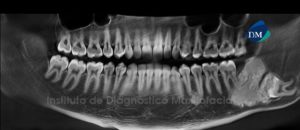

041 – Planificación y Tratamiento en Rehabilitación Oral con Prótesis sobre Implantes usando Análisis Cefalométrico

En los pacientes desdentados, que requieren una prótesis completa ya sea convencional o implanto soportada, los dientes artificiales se colocan en la prótesis completa por